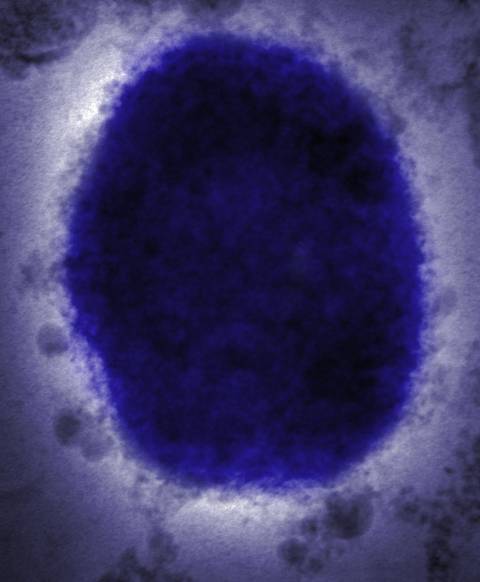

猴痘病毒通过与受感染的人、动物或受污染物质的密切接触传播,通常会引起发烧、头痛和皮疹等症状。